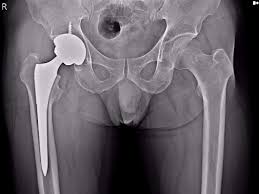

고관절 수술 후 회복 기간은 환자의 상태와 수술 방법에 따라 크게 달라집니다. 일반적으로 고관절 수술에는 두 가지 주요 유형이 있습니다. 첫째는 관절경 수술로, 최소 침습적으로 문제를 해결하는 방법입니다. 이 경우 회복 기간이 짧을 수 있습니다. 둘째는 관절 치환술로, 고관절을 인공 관절로 대체하는 수술입니다. 이 수술은 보다 복잡하며, 회복 기간이 상대적으로 더 길어진다는 특징이 있습니다.